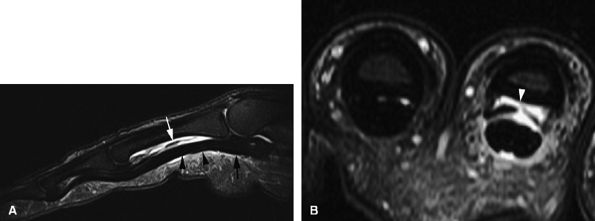

-

The cellular or solid type of glomus tumor is composed mainly of a proliferation of epithelioid cells (glomus cells) with a relative paucity of vascular lumens. This type of tumor is difficult to detect with MR imaging. Its signal is close to that of the normal dermis of the nail bed on all sequences (Fig. 11.129). Injection of gadolinium, even with MR angiography, is of little use. Using 3D gradient-echo imaging with thin contiguous slices is the most helpful by depicting a peripheral capsule or a slight bone erosion on the dorsal aspect of the phalanx.